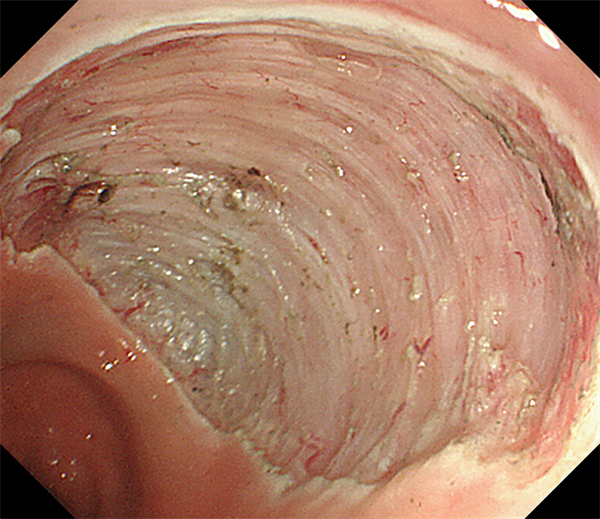

患者周某,男60岁,体检行肠镜发现直肠肿物,行肠镜下直肠黏膜下剥离术(ESD),术后病理:绒毛状管状腺瘤,局灶呈高级别上皮内瘤变。